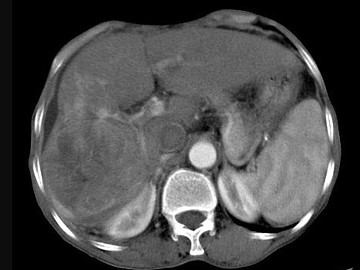

女,40岁,有口服避孕药史,肝区疼痛、腹部包块,AFP阴性,CT扫描如图,最可能的诊断是()

• A.肝细胞腺瘤

• B.肝再生结节

• C.结节性肝癌

• D.肝右叶巨块型肝癌

• E.肝黄色肉芽肿